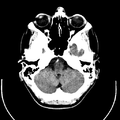

التصوير المَقْطَعي الحاسوبيX-ray computed tomography نظام تصوير بالأشعة السينية، يُسْتخدم لتصوير مختلف أجزاء الجسم مثل الرأس والقلب والبطن. ويستعين الأطباء بالتصوير المقطعي الحاسوبي على تشخيص الأمراض وعلاجها. وتسمى هذه التقنية أيضًا التصوير المقطعي المحوسب أو التصوير المقطعي المحوري المحوسب.

وللحصول على صورة أشعة مقطعية، يرقد المريض على طاولة تمر من خلال آلة فحص دائرية، تسمى المِسْند. وتوضع الطاولة بحيث يكون العضو المراد فحصه واقعًا عند منتصف المسند. وعن طريق أنبوب على المسند، تخرج أشعة سينية مخترقةً جسد المريض، ثم تدخل إلى مكشافات خاصة تقوم بتحليل الصورة التي ظهرت. ويدور المسند حول المريض للحصول على كثير من الصور من زوايا مختلفة. وبعد ذلك، يعالج الحاسوب المعلومات الآتية من المكشافات، لينتج صورة مقطعية مستعرضة على شاشة فيديو. وعن طريق تحريك الطاولة داخل المسْند، يمكن للأطباء الحصول على العديد من الفحوص للعضو نفسه، أو للجسد كله.

يمكن للأطباء أن ينظروا داخل جسم المريض عن طريق طلب إجراء مسح للعظام والأوعية الدموية والأدمغة والأنسجة الرخوة بفضل ماسح التصوير المقطعي الحاسوبي (CT). بعد إجراء أول فحص طبي بالأشعة المقطعية للمريض في عام 1971، استخدم أطباء الأشعة عمليات المسح لتشخيص الأورام والصدمات والتخطيط للعلاج الطبي والجراحي والإشعاعي في جميع أجزاء جسم الإنسان تقريباً.

داخل الجهاز على شكل كعكة الدونات، حيث يستلقي المرضى على الطاولة بينما يتحرك ببطء عبر الماسح الضوئي، تدور الآلة حولها. أثناء دورانه، يرسل شعاعاً رفيعاً من الأشعة السينية عبر الجسم، والذي يتم جمعه على الجانب الآخر من الجهاز ونقله إلى برنامج حاسوب، حيث يتم تحميله على شاشة لعرضها على تقنيي التصوير المقطعي المحوسب.